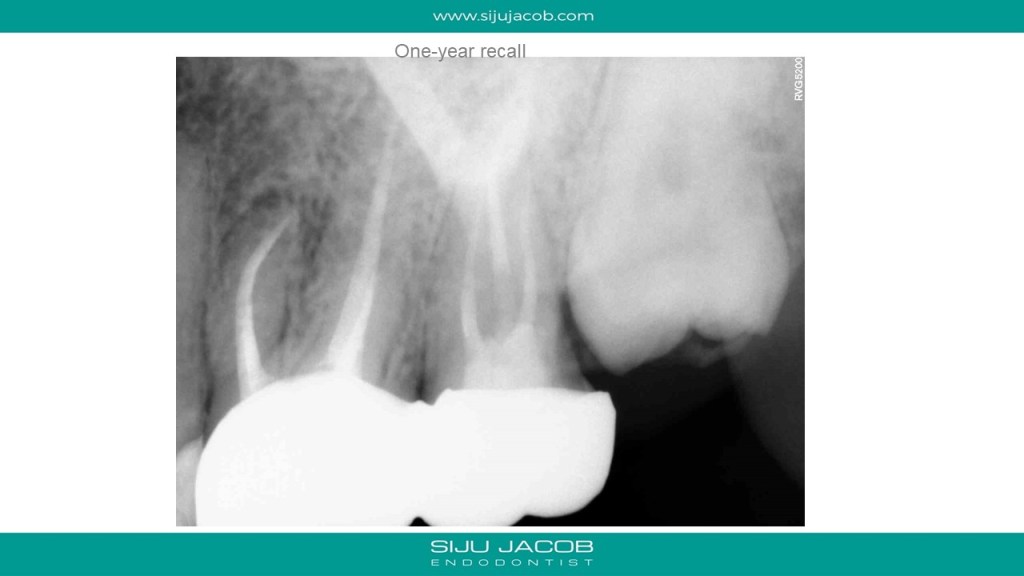

Some cases are such that when you eventually finish, you wonder what the fuss was all about. I struggled to locate the canals in this case. Not sure why. Yes, the access was difficult, but the main reason I struggled was probably the prior access that was made. This made me lose orientation initially. I managed to locate one canal and then took an Inter-appointment CBCT. This made things much easier. More in the short video below:

And below are the clinical slides of the same case: